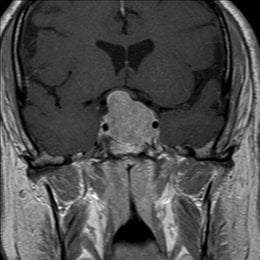

PREGUNTA 4 de 10

¿Cuál es el diagnóstico más probable de la siguiente imagen?

A)

quiste aracnoideo

B)

Quiste de la bolsa de Rathke

C)

craneofaringioma

D)

Silla turca vacía

E)

macroadenoma hipofisario